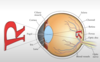

Label the diagram

Label the diagram

What is the purpose of the cornea?

- Involved in focusing light into eye

- Transparent covering over eye: is a barrier between outside world and inner eye

- Refracts light entering the eye

- NO blood vessels

- VERY sensitive to light

What is the purpose of the pupil?

- Small opening in eye by which light passes

- Size of pupil can change which can be due to light or emotion (e.g. like someone pupil dilates)

LOW light –> pupils dilate, more light into eye

HIGH light –>pupils constrict

What is the iris?

- The coloured portion of the eye

- Regulates the amount of light into the eye

What is the purpose of the lens?

- Serves by focusing light to back of eye (refracts)

- Transparent structure that helps refract light onto retina

What is the fovea?

- Indentation (small) at the back of the eye where there is high level detail processing of light

- Region where upper retinal layers are THINNED